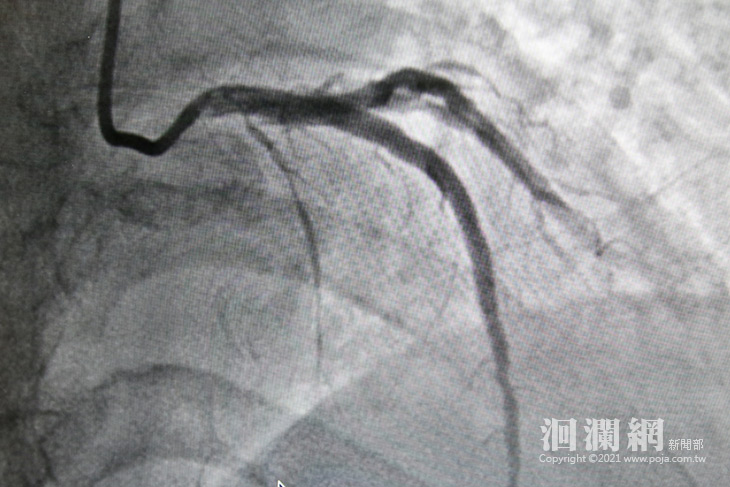

後來在一位同樣有背痛症狀的朋友建議下,張女士找到了花蓮慈院張懷仁醫師。張懷仁醫師表示,一開始很難診斷有心臟方面的問題,但是張女士提到說自己有胸悶的狀況,而且是對話一陣子就要停下來喘氣,讓張懷仁醫師擔心會不會真的是心血管的問題,結果安排心導管檢查後發現,張女士三條冠狀動脈血管中的左前降支,幾乎是完全阻塞,立即為張女士進行治療,並且放置兩條冠狀動脈血管支架。